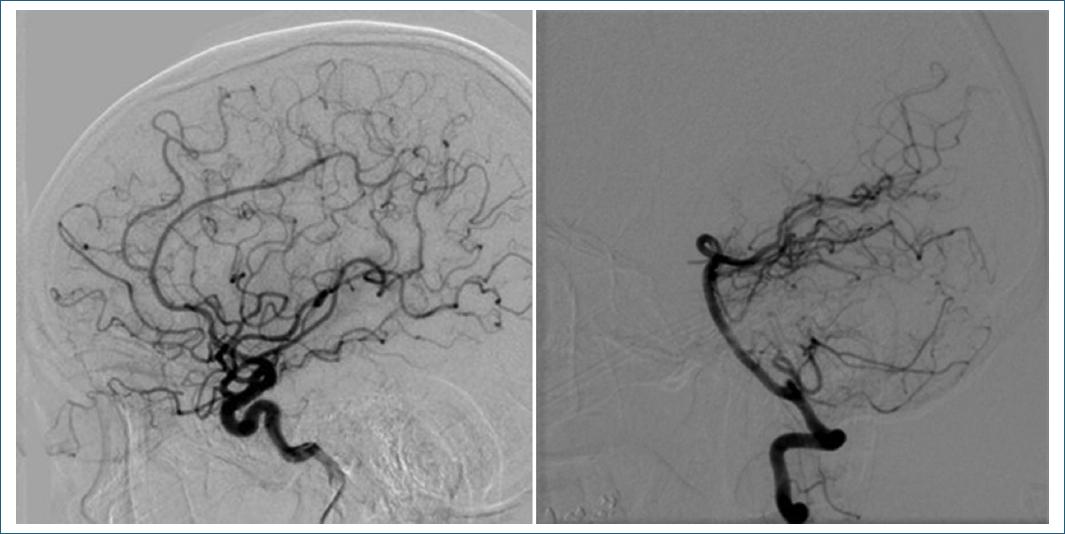

A su ingreso presentaba presión arterial de 110/80 mmHg, 88 lpm y 16 rpm. Al examen neurológico mostraba somnolencia, disartria escándida, dismetría y disdiadocosinesia de las cuatro extremidades, maniobra de Stewart-Holmes presente bilateral y rigidez de nuca; el resto de la exploración sin otros hallazgos patológicos. Se realizó tomografía computarizada (TC) de cráneo que corroboró una HIC involucrando el parénquima cerebeloso con predominio vermiano y en el hemisferio izquierdo, con un volumen estimado de 14 ml. Asimismo, se acompañaba de irrupción al espacio subaracnoideo, condicionando obliteración del IV ventrículo, sin requerir intervención quirúrgica. Durante su estancia se realizaron resonancia magnética (Fig. 1), angio-TC y angiografía diagnóstica por sustracción digital, sin evidencia de anomalía vascular estructural ni de lesiones parenquimatosas que sugirieran alguna causa de la HIC (Fig. 2). A su egreso el paciente persistió con dismetría en el hemicuerpo izquierdo, cuya mejoría sintomática le ha permitido el retorno a su actividad laboral.